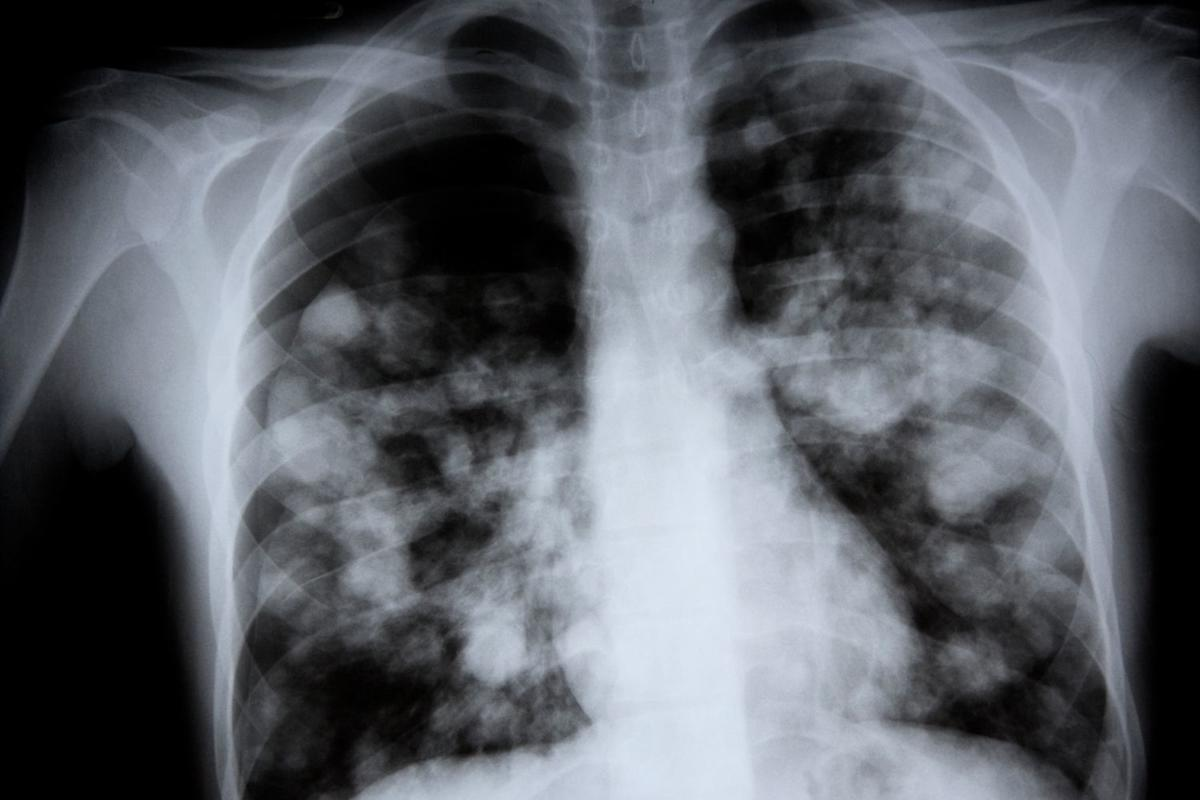

What Pneumonia Does to Your Lungs

Pneumonia causes inflammation in the air sacs of the lungs. This makes it hard for oxygen to get to the bloodstream. People with pneumonia often have a cough, fever, and trouble breathing.

The severity of these symptoms depends on the cause, age, and health of the person. In severe cases, pneumonia can lead to respiratory failure. This is when the lungs can’t get enough oxygen, and it’s very dangerous, mainly for older adults or those with health issues.